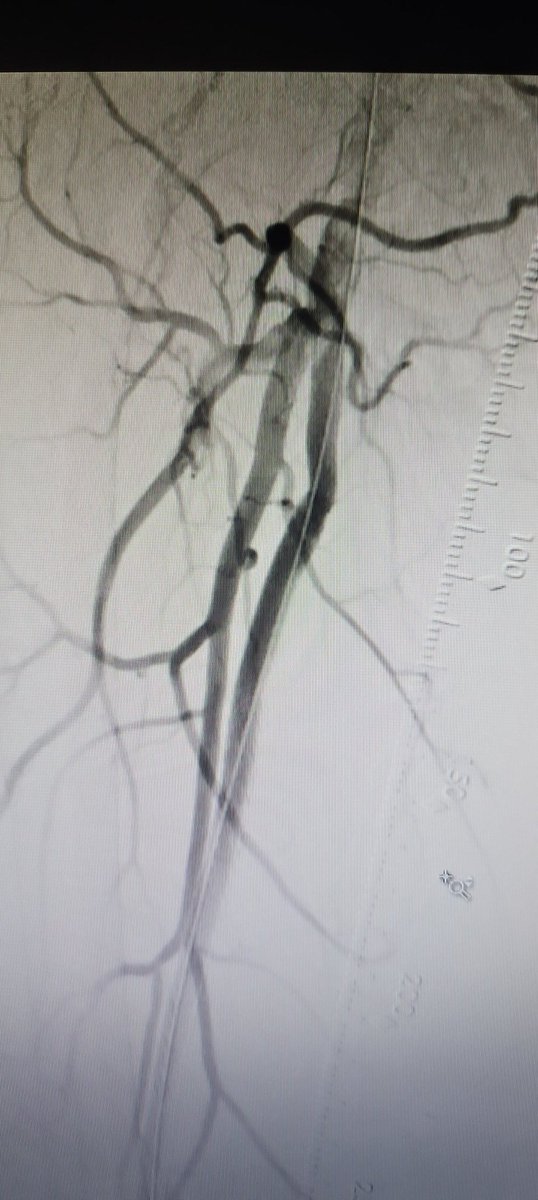

We completed the first 2 perc bypass in Illinois w #Detour @endologix Excited for this groundbreaking technology to be in the hands of #limbsalvage docs around the globe. @ShawnPenn33 @DeanFerreraDO @Abd_Alrifai @MarcoShaker @tlevin @advocatehealth

First glimpse of #PTAB w #Detour @endologix 3 week surveillance arterial duplex @ShawnPenn33 @DeanFerreraDO @MarcoShaker @kymbee @tlevin